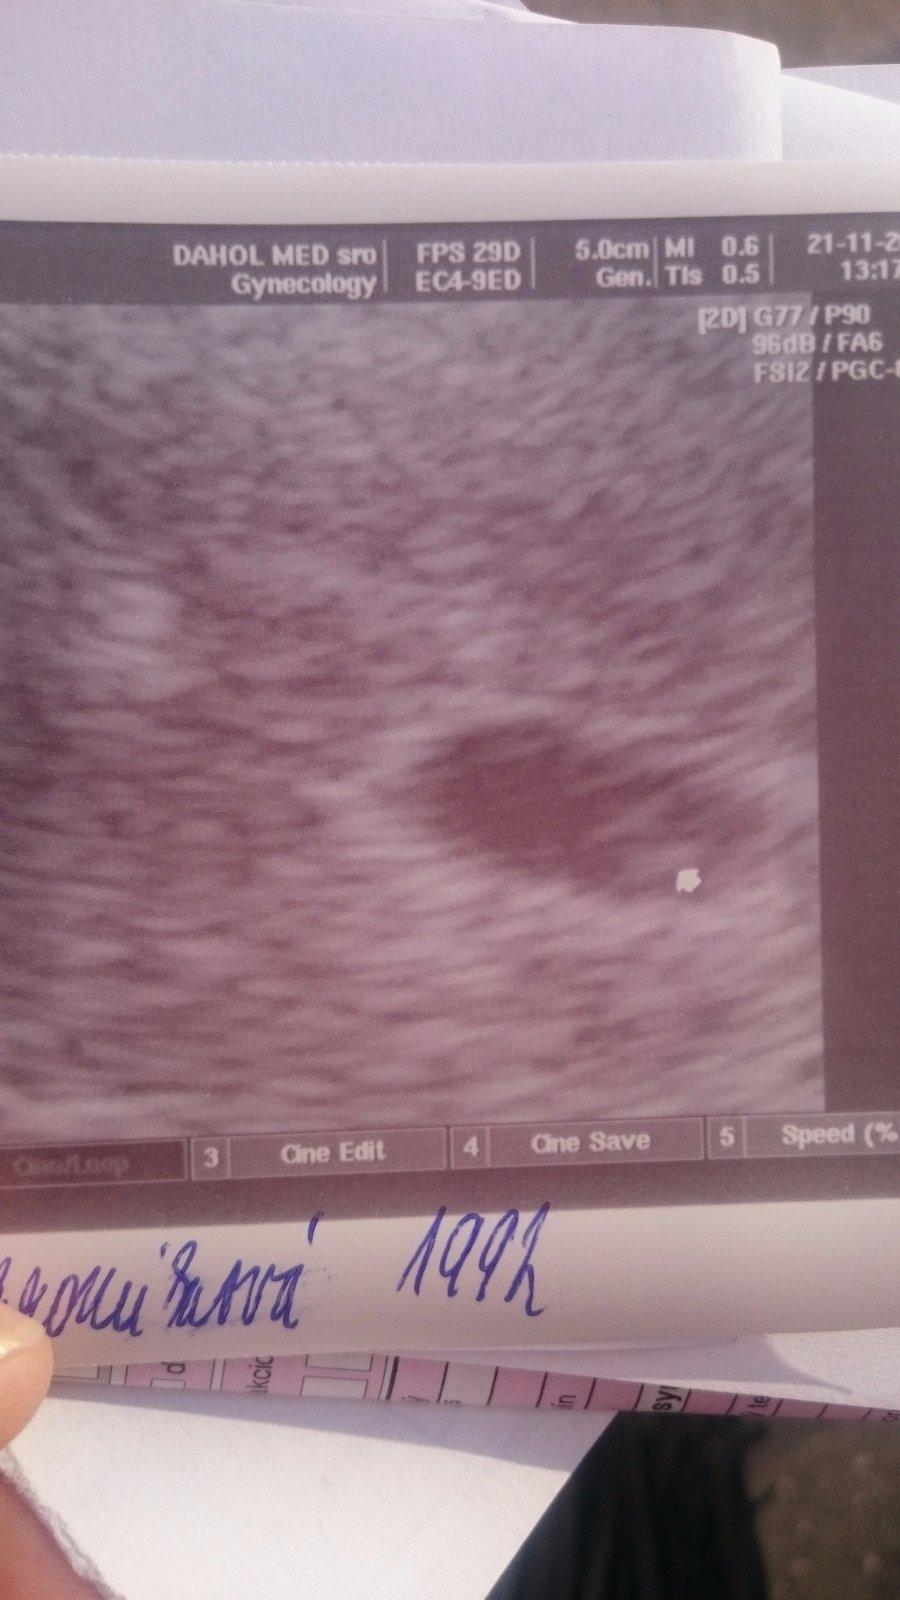

@1aduliatko1 drzim palce na vysetreni. Ja som prave vysla z ordinacie. Ardiecko nam bije 😊😊😊 a velkost presne ako vychadza 7tt+3 tak som trosku kludnejsia na chvilku. Teraz idem 19.12. Na poradnu.

Tak srdiečko nám bilo pekne, podľa sona som len 6+2 (týžden mi tam lieta) ...kontrola a na krv idem 5.12., ak bude všetko v poriadku, dostanem aj tehot. knižku 😉